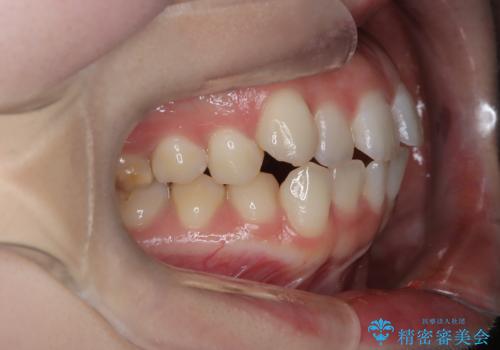

審美ワイヤー矯正とTAD併用による犬歯の遠心移動

- 歯並びの乱れを改善したいと来院されました。精密検査の結果、犬歯を奥へ動かすことで、より美しい口元と安定した咬み合わせが得られると診断。患者様のご希望から、目立ちにくい審美ワイヤー矯正を採用し、効率的な歯の移動のために**リンガルアーチとTAD(矯正用アンカースクリュー)**を併用する計画を立てました。これにより、抜歯せずにスペースを確保し、犬歯をスムーズに遠心へ移動させます。

今回の矯正では、装置が目立たないよう透明なブラケットと白いワイヤーを使用。さらに、効率的な歯の移動のために、歯の裏側にリンガルアーチを設置しました。また、確実な奥歯の移動のために**TAD(矯正用アンカースクリュー)**を一時的に使用。これにより、犬歯を狙った位置へ正確に動かすことが可能に。目立ちにくい装置で快適に過ごしながら、理想的な歯並びと咬み合わせを獲得していただけました。